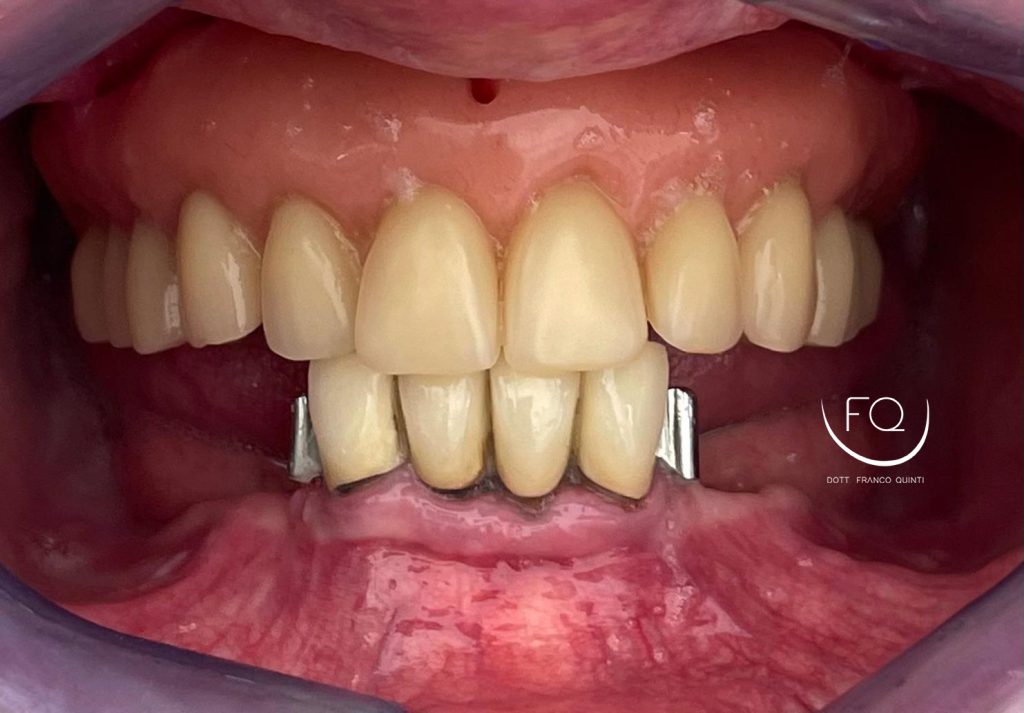

Oggi vi presento un caso di riabilitazione dell’arcata inferiore eseguito con l’utilizzo di dime scomponibili.

Il trattamento ha previsto l’inserimento di 4 impianti Prama Power di Sweden & Martina e la contestuale riabilitazione protesica provvisoria. Tra 3 mesi il caso verrà finalizzato con una protesi definitiva.